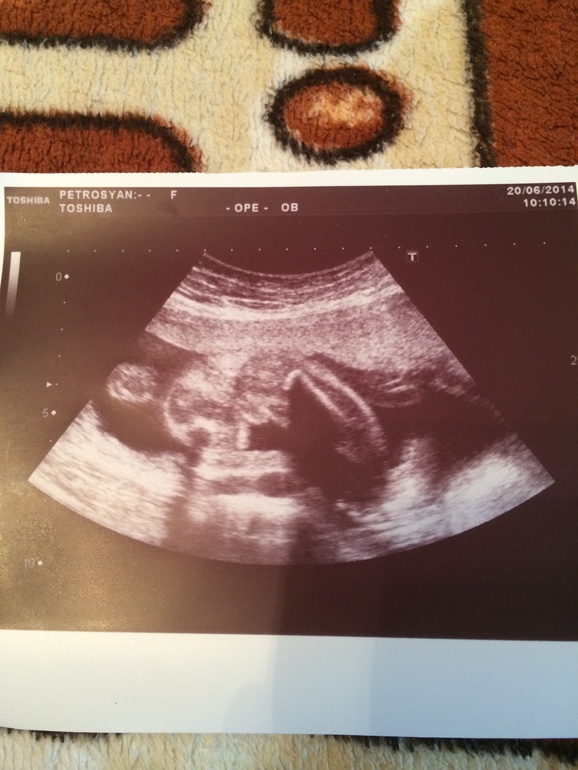

ЗаморочкиКто то с разу знает пол ребенка, а кому то 10 раз говорят и каждый раз разное))) посмотрите фото узи пожалуйста( срез снизу 23-24 неделя) в процессе просмотра была девочка, а когда врач распечатать снимок, то говорит мальчик))) а Вам как кажется?

У нас вчера на УЗИ яйки как-то покруглее были (срок на неделю меньше), а тут может быть и пирожок. Сходите на ЗД УЗИ, и сомнения развеются и память на всю жизнь (видео на диске).

Я в снимках вообще не разбираюсь, даже не знаю куда смотреть и на что))) но узор на пледе как бы намекает на мальчика)))))))))))